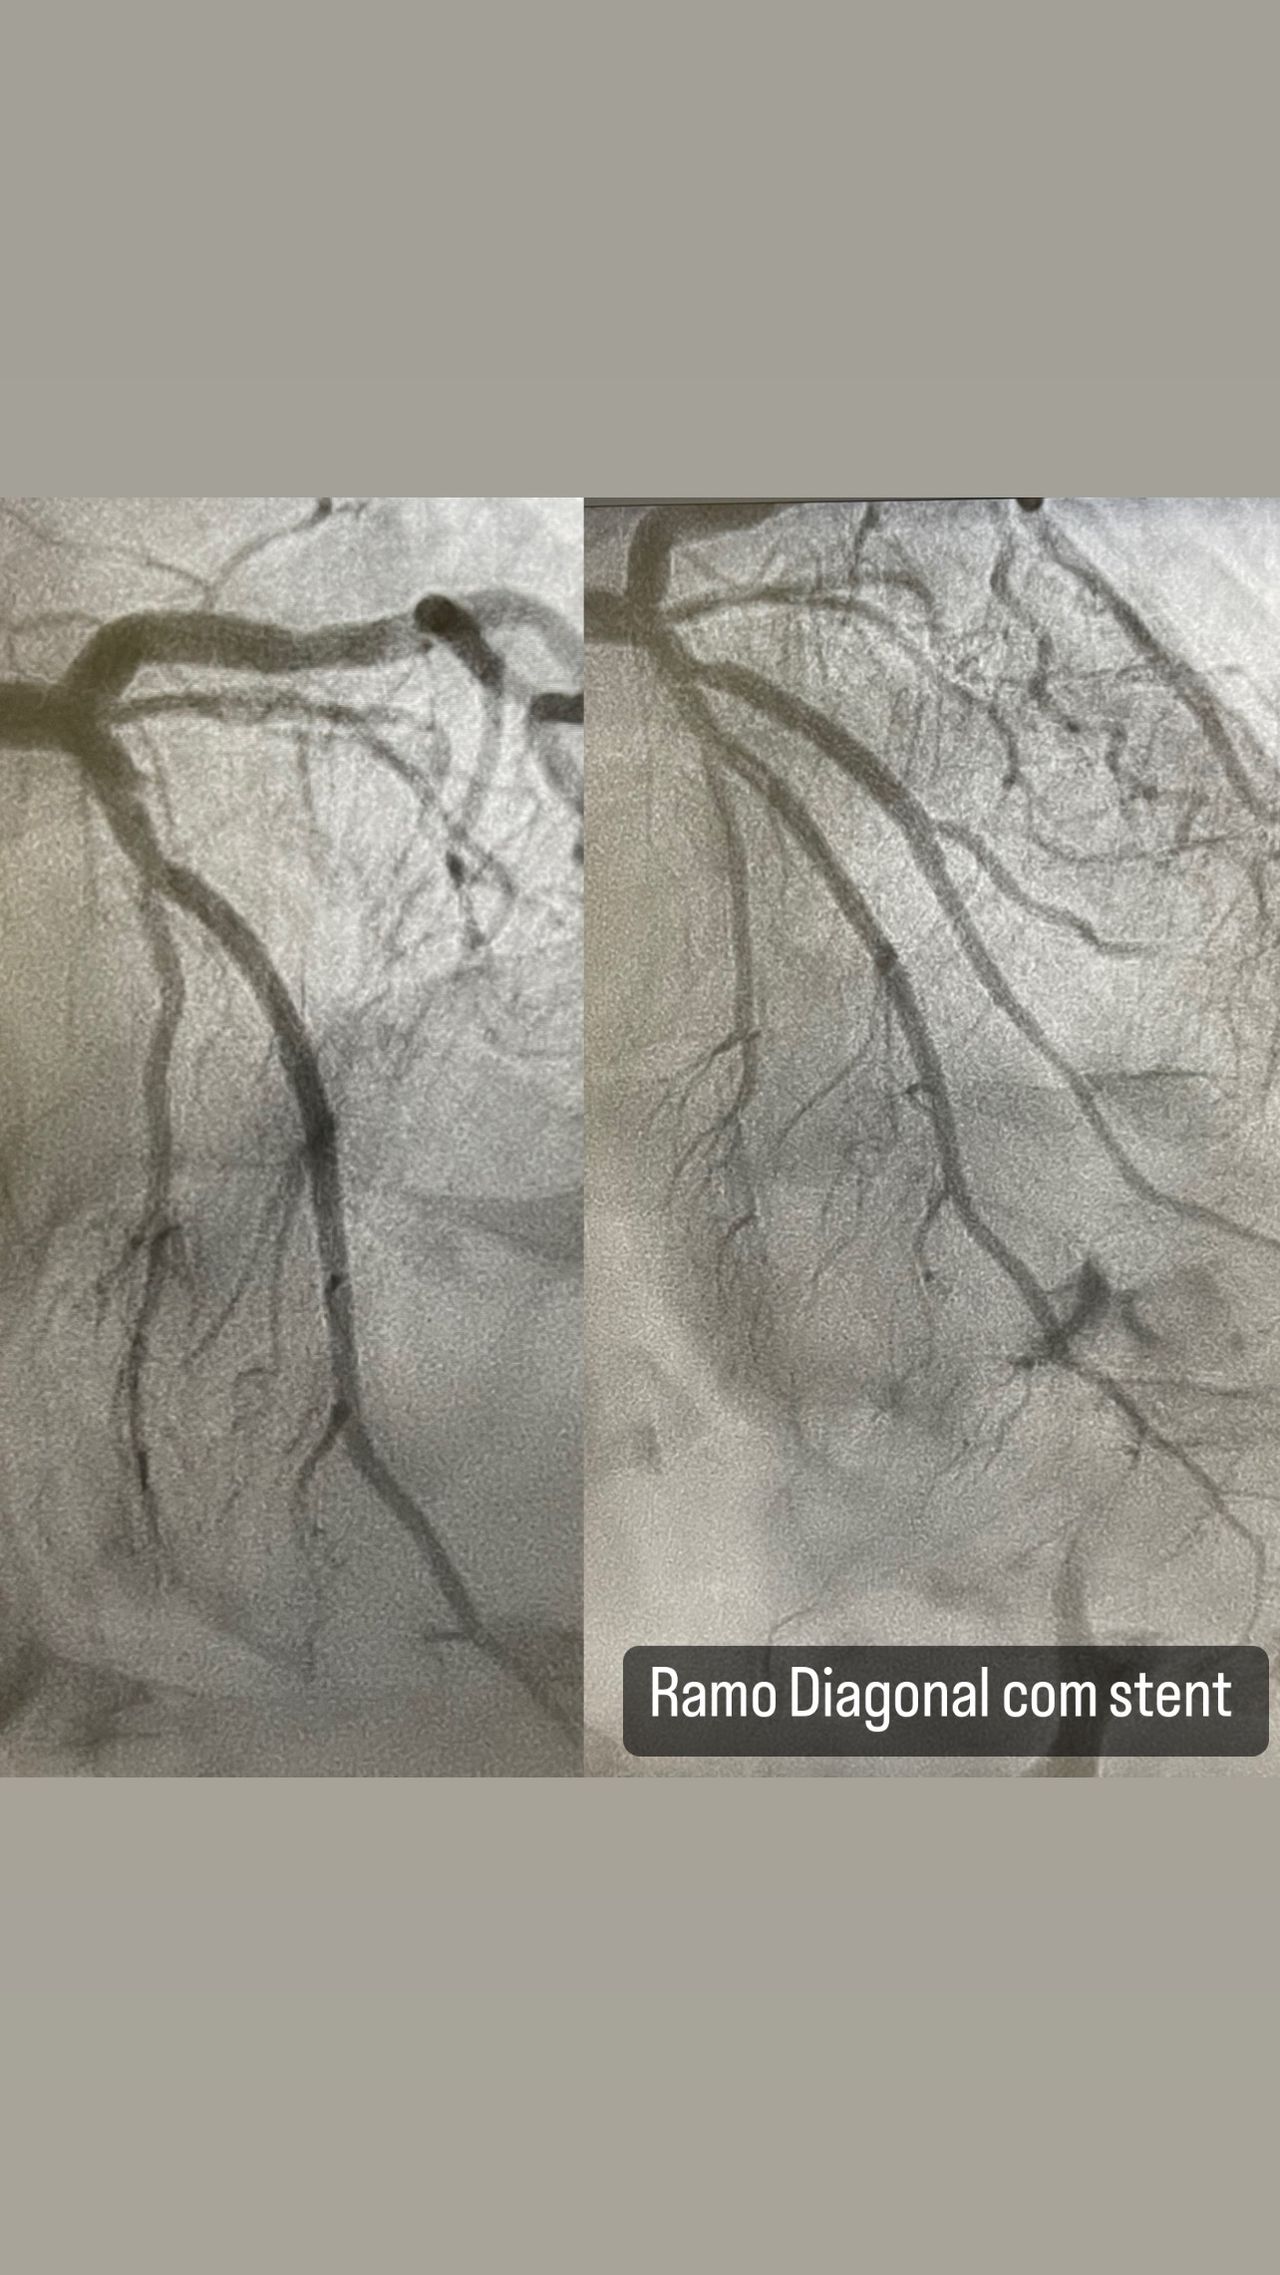

Realização de tratamentos minimamente invasivos no coração: cateterismo cardíaco (estudo das artérias do coração), angioplastia coronariana (implante de stent) e tratamentos das doenças que acometem as válvulas do coração.

Os procedimentos são realizados através da punção das artérias dos braços ou das pernas do paciente. É o tratamento mais seguro e eficaz para angina (dor no peito), infarto do miocárdio, obstruções (estenoses) nas artérias do coração e doenças das válvulas do coração ("sopros").

- Hemodinâmica e cardiologia intervencionista

- Doença arterial coronária

- Cardiologia intervencionista